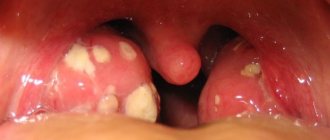

2. Тонзиллит. При этом заболевании образуются карманы гноя, которые просматриваются как белые пятна на миндалинах.

• красные, рыхлые, отекшие миндалины с налетом гноя;

• Особым внешним видом. Если заглянуть в здоровое горло человека, то можно увидеть миндалины с гладкой, ровной и розоватой поверхностью. А если осмотреть воспаленное горло с рыхлыми миндалинами, то можно отметить, что горло стало красным, а поверхность гортани — неровной. Миндалины покрываются бугорками красного или желтоватого цвета, это места нагноения. Они покрываются бело-желтым налетом.

• В диагностических целях могут назначить фарингоскопию. При тонзиллите картина типичная:

• мягкое небо

• гипертермия и отечность миндалин

• наличие в лакунах миндалин гноя

• наличие бело-желтого налета.